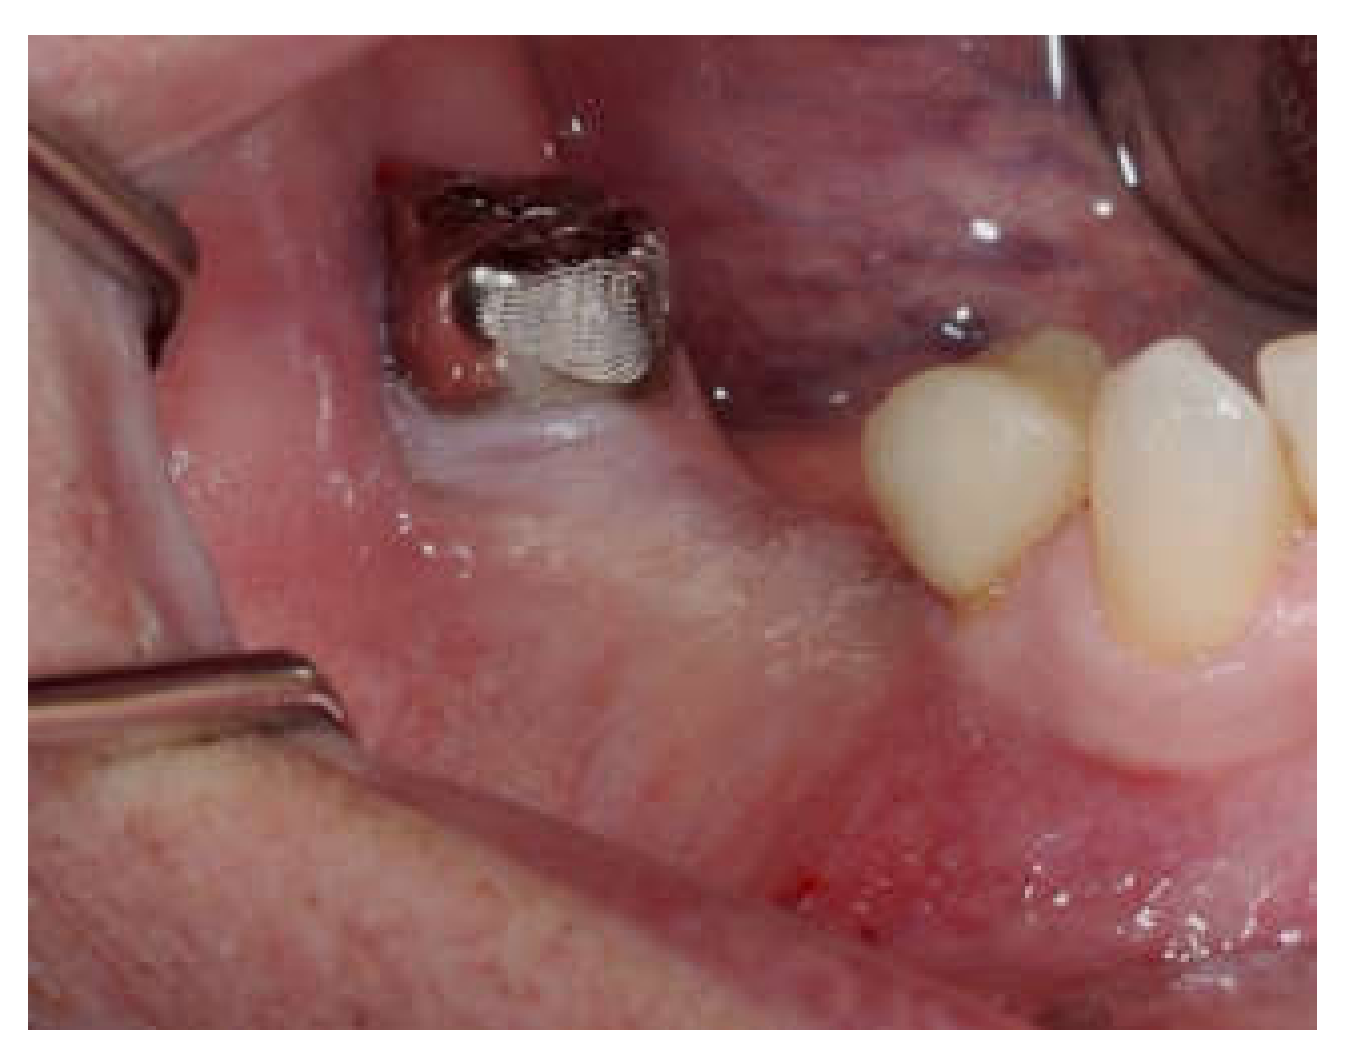

Clinical and CBCT aspects of patient from the test group, describing the stages of S-GBR technique and implant-prosthetic stage, are presented in Figure 1, Figure 2, Figure 3, Figure 4, Figure 5, Figure 6, Figure 7, Figure 8, Figure 9, Figure 10 and Figure 11. CBCT exam allows the evaluation of the horizontal alveolar bone defect and the position of the mandibular alveolar nerf (Figure 1A,B). Figure 1C,D show cross-sectional CBCT aspects of the implant sites. Figure 2 shows the narrowed mandibular alveolar bone with horizontal resorption. Figure 3 shows the exposed buccal surface of the alveolar ridge with severe horizontal resorption, after flap opening. The inserted implants (4.5 mm diameter, 11.5 mm length) and osteosynthesis screws (45° from the occlusal plan) are shown in Figure 4A. The placement of graft (autologous bone and xenograft) and collagen membrane is shown in Figure 4B. Figure 5A shows tension-free sutures, due to periosteal incisions alveolar ridge. Figure 5B shows clinical aspect at 7 months after surgery, with gingival tissue adherent on the reconstructed alveolar ridge. Figure 6 shows OPG aspect at follow-up of 7 months, with osseointegration of the dental implants. Figure 7A shows clinical aspect before osteosynthesis screws removal. Figure 7B shows clinical aspect after osteosynthesis screws removal. Figure 8A shows healthy peri-implant soft tissues. Figure 8B shows repositioning key for perfect position of abutments. Figure 10A,B show clinical aspects of implant-supported prosthetic restoration. Figure 11A,B show CBCT aspects of Osseo integrated dental implants at 24 months follow-up.

Figure 2.

Pre-operative clinical aspect of the narrow residual ridge.